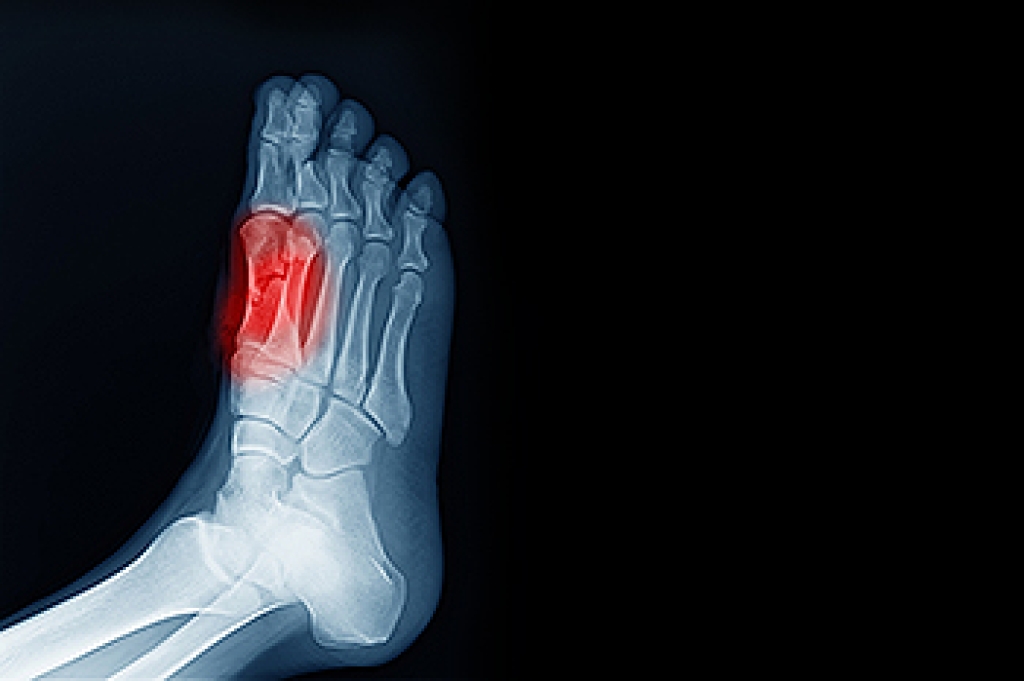

The group of bones that are under the bottom of the big toe include the sesamoid bones. They protect specific tendons in the foot, and absorb most of the weight on the inside of the foot. The condition that is known as sesamoiditis occurs when the sesamoid bones become inflamed. They can become injured as a result of enduring a stress fracture, or from an injury that comes from repetitive motion consisting of dancing. Many patients need to have a proper diagnosis performed, which includes having an X-ray taken that can rule out a fracture. Correct treatment techniques can possibly reduce painful symptoms, in addition to protecting the foot from further injury. These can consist of wearing orthotic insoles, taking anti-inflammatory medication, or possible surgery. If you feel you have injured your sesamoid bones, it is strongly urged that you confer with a podiatrist who can help you to manage this condition, in addition to offering you correct treatment solutions.

Sesamoiditis is a condition of the foot that affects the ball of the foot. It is more common in younger people than it is in older people. It can also occur with people who have begun a new exercise program, since their bodies are adjusting to the new physical regimen. Pain may also be caused by the inflammation of tendons surrounding the bones. It is important to seek treatment in its early stages because if you ignore the pain, this condition can lead to more serious problems such as severe irritation and bone fractures.